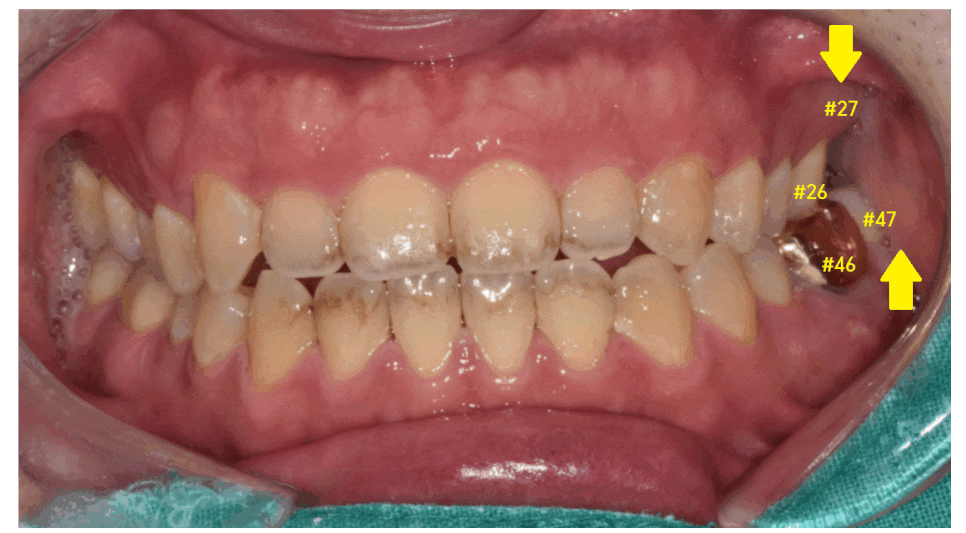

구강 내 사진을 보겠습니다.

#17 맨 끝 어금니가 한 개가 없네요.

이 경우에는 교합을 확인합니다.

앙~ 물어보세요.

23.03.12

#47 오른쪽 아래 맨 끝에 치아가

#16 오른쪽 제 1큰 어금니와 물리네요.

#17 맨 뒤에 치아가 없지만

물리기 때문에

이 경우는 임플란트를 안 해도 됩니다.

구강 내 사진에서도 이가 한 개가 없죠~?

교합되는 사진을 보겠습니다.

#27 왼쪽 맨 끝 치아가 상실

#47 왼쪽 아래 맨 끝 치아가 물리는 게 없네요~